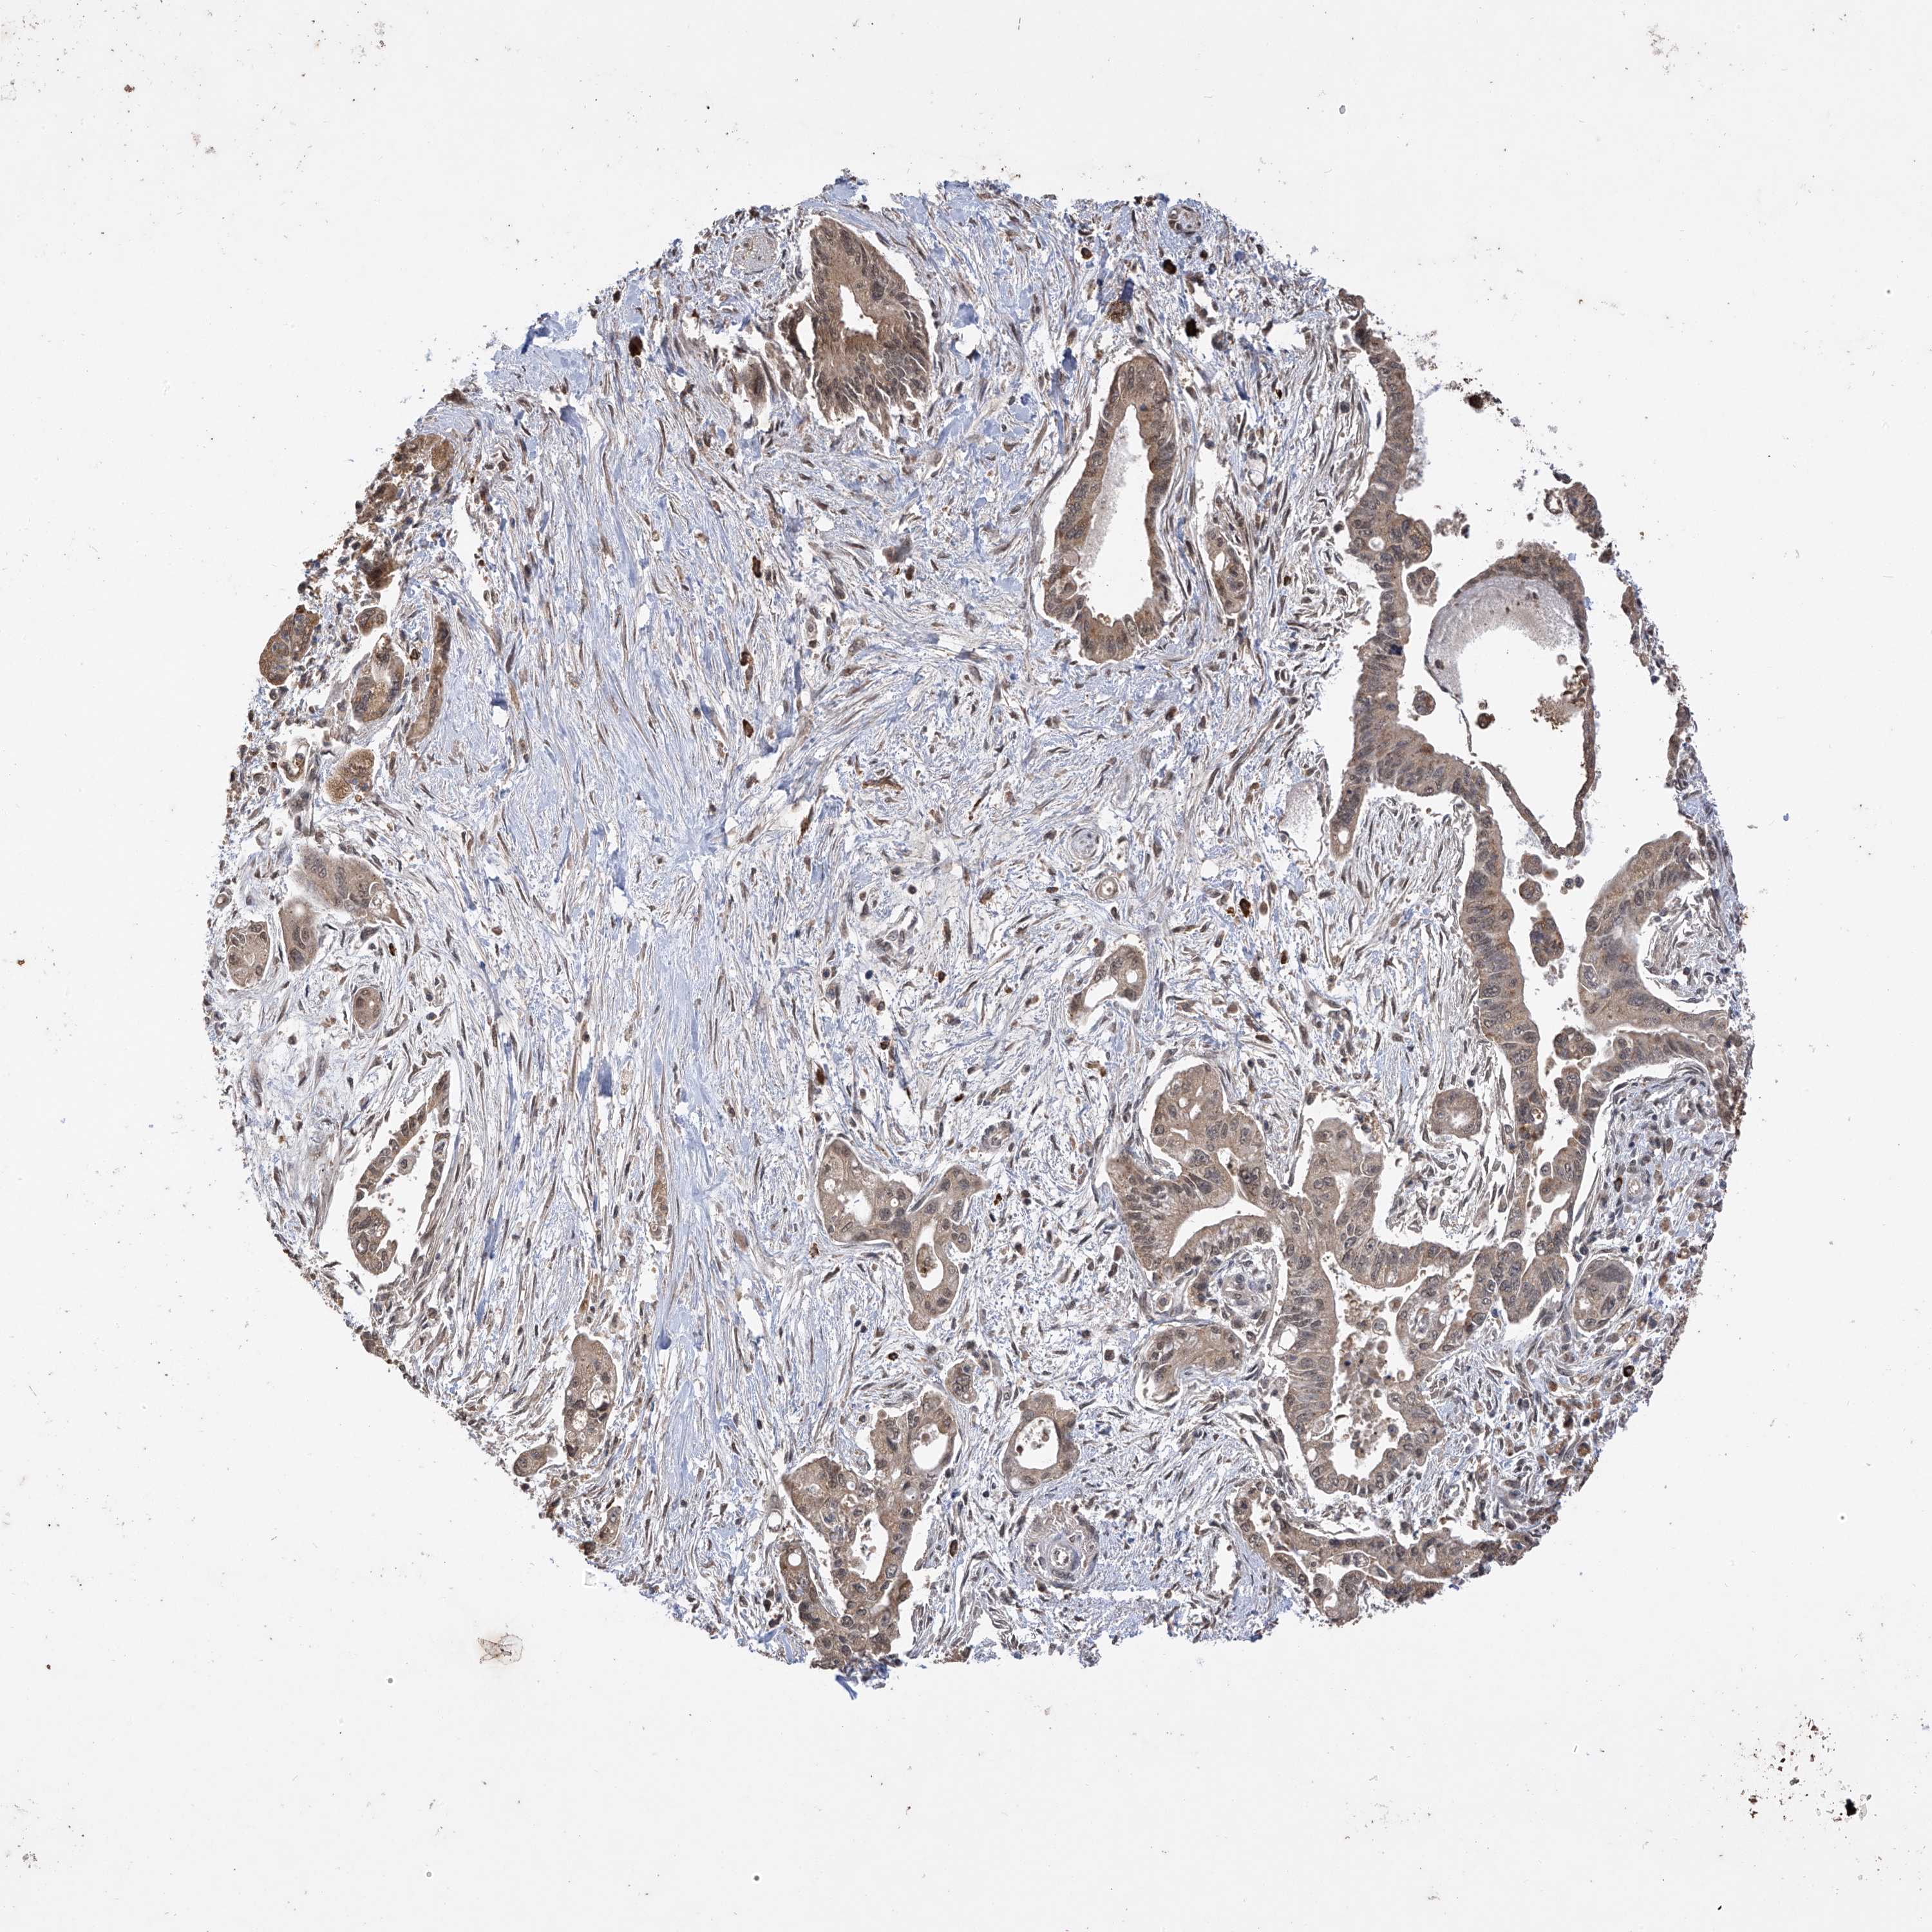

PANCREATIC CANCER - Protein expressioni

A mouse-over function shows sample information and annotation data. Click on an image to view it in a full screen mode. Samples can be filtered based on level of antibody staining by selecting one or several of the following categories: high, medium, low and not detected. The assay and annotation is described here.

Note that samples used for immunohistochemistry by the Human Protein Atlas do not correspond to samples in the TCGA dataset.

Antibody stainingi

Antibody staining in the annotated cell types in the current human tissue is reported as not detected, low, medium, or high, based on conventional immunohistochemistry profiling in selected tissues. This score is based on the combination of the staining intensity and fraction of stained cells.

Each image is clickable and will lead to virtual microscopy that enables deeper exploration of all samples and also displays staining intensity scores, fraction scores and subcellular localization as well as patient and tissue information for each sample.

Antibody HPA034602

Antibody HPA034603

Antibody CAB033424

Staining

High

Medium

Low

Not detected

Intensity

Strong

Moderate

Weak

Negative

Quantity

>75%

75%-25%

<25%

None

Location

Nuclear

Cytoplasmic/membranous

Cytoplasmic/membranous,nuclear

Adenocarcinoma, NOS